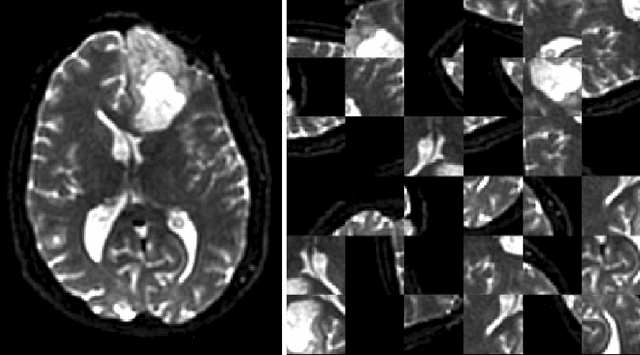

Translating neural networks from theory to clinical practice has unique challenges, specifically in the field of neuroimaging. In this paper, we present DeepNeuro, a deep learning framework that is best-suited to putting deep learning algorithms for neuroimaging in practical usage with a minimum of friction. We show how this framework can be used to both design and train neural network architectures, as well as modify state-of-the-art architectures in a flexible and intuitive way. We display the pre- and postprocessing functions common in the medical imaging community that DeepNeuro offers to ensure consistent performance of networks across variable users, institutions, and scanners. And we show how pipelines created in DeepNeuro can be concisely packaged into shareable Docker containers and command-line interfaces using DeepNeuro's pipeline resources.